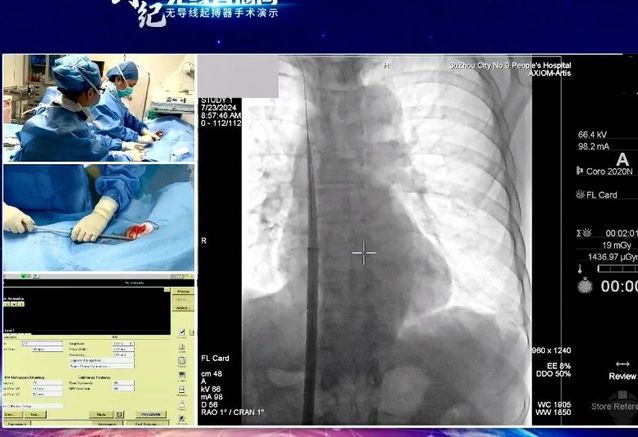

7月24日,“创势纪·无线直播间—苏皖区域无导线起搏器手术演示”在线上举行,苏州九院心血管内科主任吴雁鸣参与手术演示,助力提升区域心血管病防治水平。本次活动由江苏省医学会心血管病学分会副主任委员、苏州市心血管病学分会主任委员、苏州大学附属第一医院心内科主任蒋廷波主持,汇聚了一大批专家教授开展手术演示和线上探讨,通过学术交流积极推动苏皖地区心血管病防治水平的进一步提高。

早在2021年,苏州九院心血管内科就积极引入和开展无导线心脏起搏器植入术,是我区首家成功独立开展无导线起搏器植入手术的医院。心血管内科主任吴雁鸣是我区首位独立无导线起搏器术者,目前已成功独立植入近30例,受益人群大多为高龄老人,其中年龄最大的患者接受手术时已经103岁。